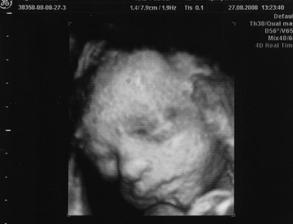

26.8.2008 ( 26.tt ) jsme jeli do Liberce na 4D utz,ale jelikož tam byl doktor,který tomu prd rozuměl a i záběry stáli za prd,tak jsem hned druhej den ráno volala,že jsem nespokojená a tak mi paní doktorka nabídla,at přijedu znovu a tak jsem s tchynkou nasedla na vlak a jeli jsme tedy 27.8.2008 a záběry máme opravdu krááásné a ty zážitky a vzpomínky 🙂 Prostě nááádhera,vím jistě,že jak budu podruhé těhotná,že tam pojedu znovu !!!